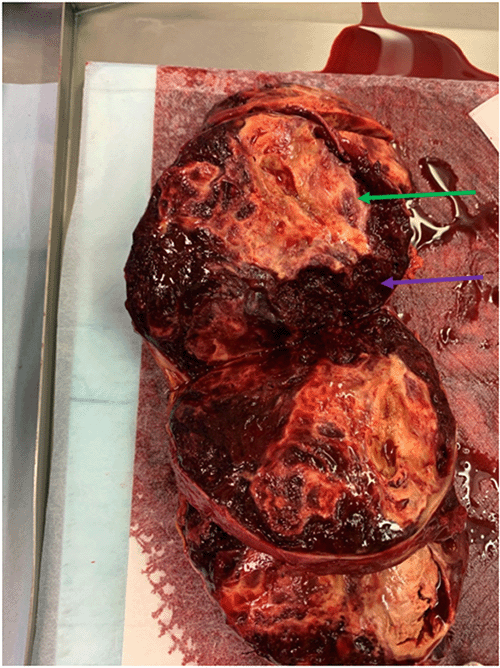

Figure 1. Cross-sectional Imaging of Abdomen. Published with Permission

A) Preoperative CT scan displaying a large right-sided adrenal angiosarcoma

B) imaging post-surgery following resection of the right adrenal angiosarcoma

The pathology result for the right adrenal tumor was epithelioid angiosarcoma with extensive surrounding hemorrhage, with negative tumor margins and an intact capsule. Consultation with the Department of Pathology at Brigham and Women’s Hospital confirmed this diagnosis, showing atypical endothelial cells with epithelioid morphology, amphophilic cytoplasm, and vesicular nuclei. The specimen stained positive for CD31 and ERG (ETS-related gene, an oncogene). Figure 1 shows cross-sectional imaging of the abdomen before and after the surgery. Figures 2 and 3 show the gross specimen (green arrows point to the tumor, and the purple arrow to the associated hematoma). Figures 4 and 5 show the microscopic histopathologic view of the specimen (green arrow points to the atypical endothelial cells, purple arrow to the hematoma).

The patient continued to do well postoperatively and followed up in the clinic. Based on the pathological diagnosis, the patient’s medical oncologist completed staging with a CT of the chest and head, which did not reveal evidence of metastases. A surveillance abdominal CT scan was obtained by oncology six weeks postoperatively and did not suggest any residual disease or recurrence of the tumor.